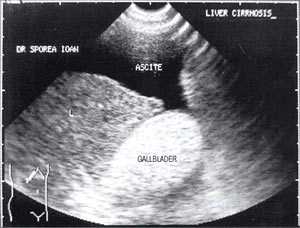

Рассматривая этиологию "желчного сладжа", его можно классифировать на вторичный и первичный. Вторичный сладж появляется, когда имеется хорошо известное этиопатогенетическое условие: после ударно-волновой литотрипсии по поводу желчных конкрементов, при желчно-каменной болезни, беременности [3, 4], циррозе печени, механической желтухе, водянке желчного пузыря, длительном парентеральном питании [5,6], сахарном диабете, серповидно-клеточной анемии [7], после приема цефтриаксона [8, 9]. Как первичный сладж расценивается в тех случаях, когда не может быть выявлено ни одно из указанных выше состояний.

В исследовании, проведенном в США, "желчный сладж" выглядел в виде гиперэхогенного образования в желчном пузыре с горизонтальным уровнем без задней тени, форма которого медленно изменялась при движении больного [10]. Характерный признак "желчного сладжа" - изменение его вида на сканограмме в зависимости от изменения положения тела больного и медленным достижением нового горизонтального уровеня. Общим правилом является отсутствие дистальной акустической тени. Эхогенность сладжа может быть различной. Иногда сладж заполняет весь желчный пузырь, затрудняя дифференцировку между тканью печени и желчным пузырем. Эта ситуация называется "гепатизация желчного пузыря" (рис. 1).

Рис. 4. "Желчный сладж" у больного с циррозом печени.

Рис. 5. Желчный пузырь, заполненный сладжем, у больного циррозом.